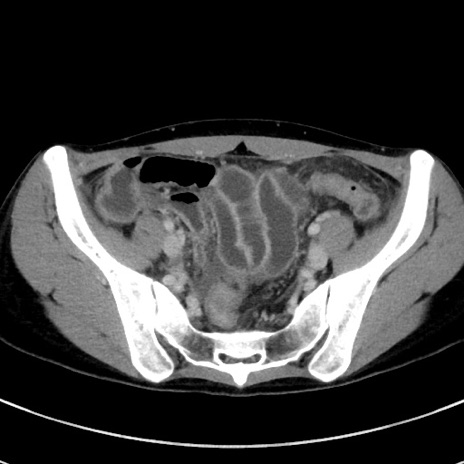

冠状断像

【症例】20歳代女性

【主訴】嘔吐、下腹部痛

【現病歴】昨日夕食後に嘔吐し下腹部痛が出現。本日になっても嘔吐持続し改善しないため来院。

【身体所見】意識清明、BT 37.2℃、BP 108/67mmHg、腹部:平坦、やや硬、下腹部正中から右にかけて圧痛あり、反跳痛軽度あり、tapping pain(+)。

【データ】WBC 13600、CRP 14.94